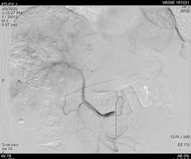

于2019年10月10日复查,检查肝增强CT示,肝脏多发占位性病变,考虑原发性肝癌,部分病变为TACE治疗后改变,其内可见肿瘤存活,对比2019年8月17日病变增多增大,碘油沉积增多。再次DSA引导下行TACE治疗。

图片

图:肝增强CT(2019-10-10)